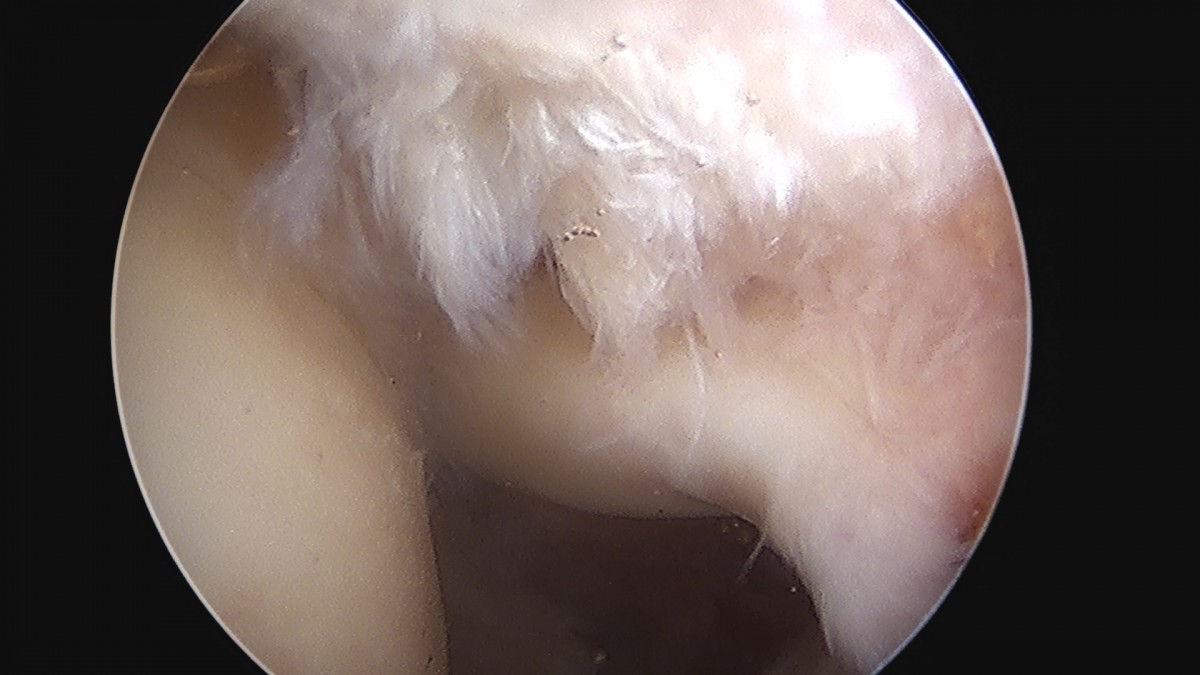

이재상원장님 어깨 이두박건 절제술 정하O 환자

dae765e4d9ac96aee867c9d6292d8784_1758006930_754.jpg